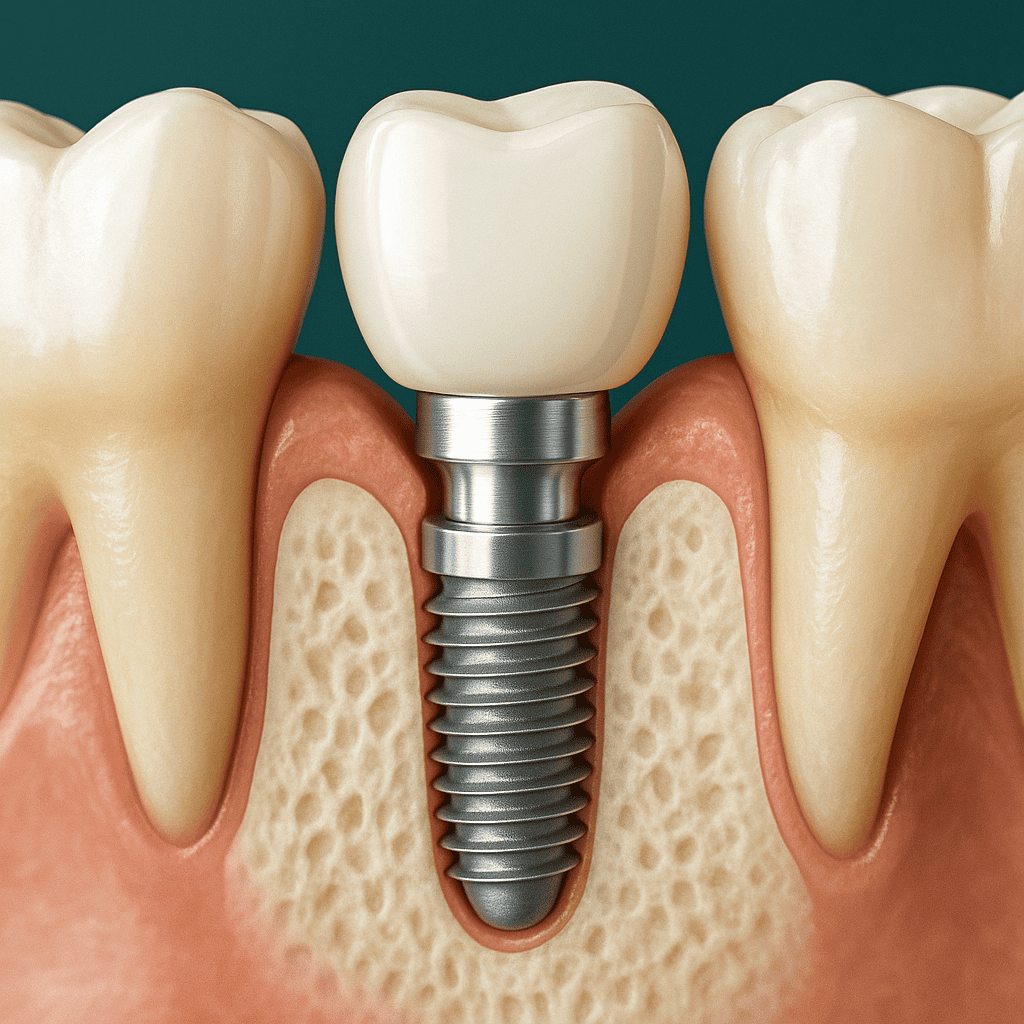

Qual è la differenza tra impianti in titanio e impianti in zirconia?

Impianti in titanio: il titanio è utilizzato da oltre 40 anni in implantologia. È un metallo altamente biocompatibile ed estremamente resistente, che si integra perfettamente con l’osso (osteointegrazione). Gli impianti in titanio sono spesso composti da due parti (radice + pilastro), permettendo così un’ampia adattabilità ai diversi tipi di protesi.

Quale impianto scegliere? Il titanio resta lo standard di riferimento, soprattutto nei casi complessi o per le riabilitazioni posteriori. La zirconia è invece preferita per motivi estetici e nelle zone visibili. In Turchia, la scelta viene sempre definita dopo una valutazione clinica completa.

Inserimento dell’impianto

In anestesia locale, l’impianto viene inserito nell’osso mascellare. Se necessario, può essere eseguito un innesto osseo. La procedura dura generalmente tra 30 minuti e 1 ora per impianto.

È previsto un periodo di 3–6 mesi affinché l’impianto si integri perfettamente con l’osso. Nel frattempo può essere posizionata una protesi provvisoria in attesa della corona definitiva.

Posizionamento della corona definitiva

Una volta completata l’integrazione, viene fissata una corona in ceramica o in zirconia, progettata per armonizzarsi con i denti vicini e garantire una masticazione confortevole e naturale.